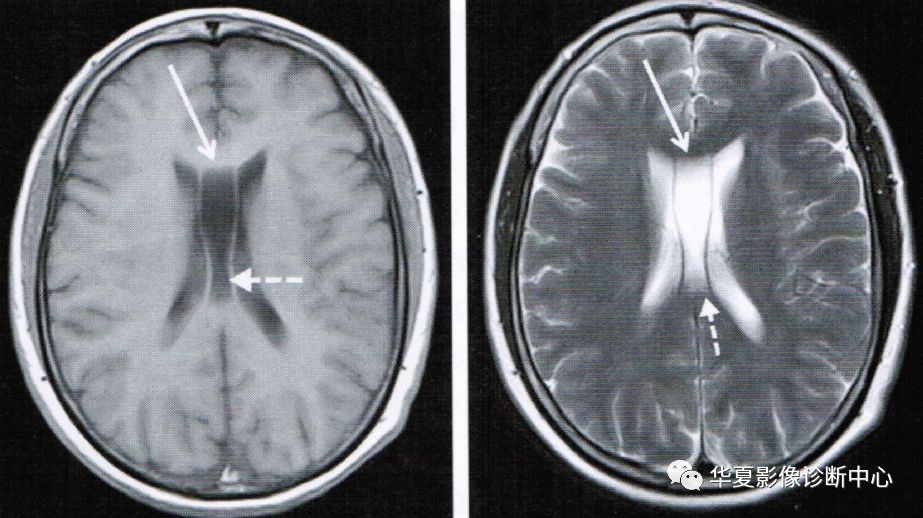

上图为第五脑室

上图为第五脑室(实箭头)、第六脑室(虚箭头)